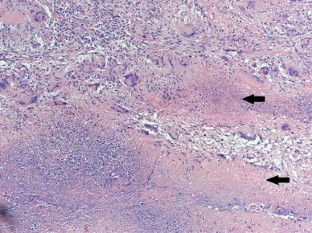

The mean age was 38.24 ± 11 (range 15–64) years. Elevated levels of serum CA125 were determined in all 28 patients (100 %). Other common findings were ascites in 20 (71.43 %, 20/28), pelvic mass in 21(75 %, 21/28), slight fever with night sweat in 13 (46.43 %, 13/28), cough and pleural effusion in nine (32.14 %, 9/28), high fever more than 39 °C combined with abdominal pain and elevated white blood count in five (17.86 %, 5/28), weight loss more than 5 kg at admission in six (21.43 %, 6/28). Diagnoses were made based on biopsy from laparotomy in 14 (50 %) patients, from laparoscopy in nine (32.14 %), from diagnostic curettage because of primary infertility in two (7.14 %), and only from clinical suspicion in three patients. Histopathology revealed that caseating granulomatous lesions were seen in 25 patients, positive anti-acid staining in 11 patients. Totally 26 patients completed anti-TB therapy successfully and were cured, two patients died of the disease because of long-term immune inhibitor used.

Fig. 4